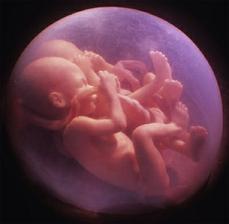

Jak asi víte, těhotenství je členěné na tři časové úseky, kterým říkáme trimestry – každý z nich trvá tři měsíce. Každý z trimestrů je zcela specifický, probíhají v něm určité charakteristické změny, podstupuje se vyšetření a nesou s sebou jiné pocity a obavy nastávající maminky.

- II. trimestr = 13. - 28. týden těhotenství

zázrak lidské života na videu